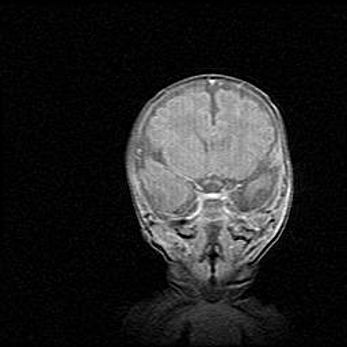

Сообщающаяся гидроцефалия. Кистозная энцефаломаляция головного мозга.

Возраст: 3 месяца 4 дня

Вес: 3100 г

Пол: женский

Окружность головы: 34 см

Срок гестации: 31 неделя

Кистозная энцефаломаляция головного мозга - одна из форм поражения головного мозга в детском возрасте. Характеризуется возникновением множественных и распространённых кист в коре, белом веществе и подкорковых образованиях головного мозга у плодов, новорождённых и детей раннего возраста. Развитие кистозной энцефаломаляции связано с внутриутробной асфиксией и гипотонией, родовой травмой, тромбозом синусов, пороками развития сосудов, инфекциями, сепсисом и другими причинами. Наиболее значимые инфекционные агенты: вирусы простого герпеса, цитомегалии, краснухи, токсоплазмы, энтеробактерии, золотистый стафилококк и другие.